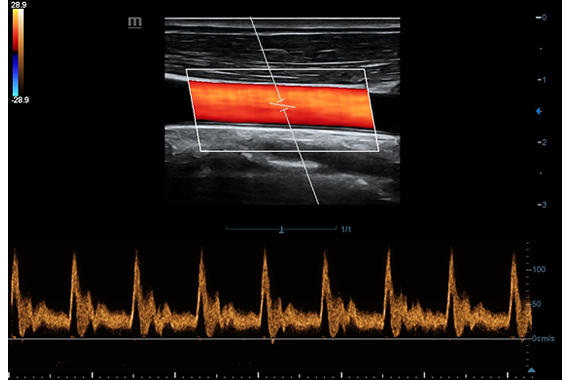

• HR Flow - режим отображения кровотока с высоким временным и пространственным разрешением для точной и однородной визуализации сосудов, в том числе самых мелких.

• HR Flow - режим отображения кровотока с высоким временным и пространственным разрешением для точной и однородной визуализации сосудов, в том числе самых мелких